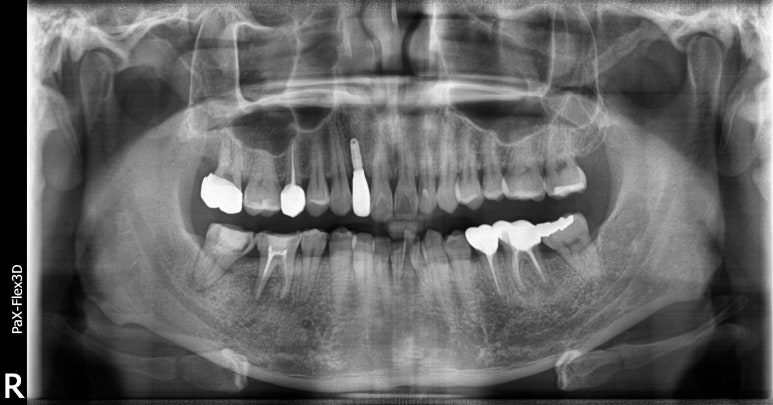

20대임플란트 실제 사례

28세 남성

(전) 2022-07-07 (후) 2022-09-02